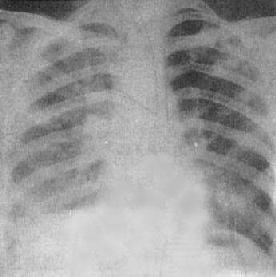

粟粒型肺结核病灶小,透视常难以辩认,故拟诊急性粟型肺结核时应摄片检查。病变早期整个肺野可呈毛玻璃样密度增高。约10日后可出现均匀分布的1.5~2mm大小、密度相同的粟粒状病灶,正常肺纹理常不能显示(图3-1-22)。经过适当治疗后。病灶可在数月内逐渐吸收,偶尔以纤维硬结或钙化而愈合。病变恶化时,可以发生病灶融合,表现为病灶增大,边缘模糊,甚至形成小片状或大片状影,并可干酪样化而形成空洞。

图3-1-22 急性粟粒型肺结核

两肺野布满粟粒状病灶,分布均匀,肺门大

(2)亚急性或慢性血行播散型肺结核:系少量结核杆菌在较长时间内多次进入血流播散至肺部所致。患者抵抗力较强,症灶多以增殖为主,临床症状可不明显或有反复的发热、畏寒或轻度结核中毒症状如低热、盗汗、无力、消瘦等。